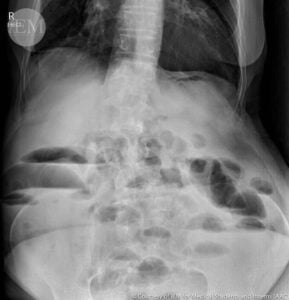

Диагностика на болката в корема

Диагностицирането на причината за коремна болка може да бъде предизвикателство, тъй като има много възможни причини. Вашият лекар или лекари би трябвало да започне със снемане на подробна анамнеза и извършване на физически преглед.

Те могат също да назначат диагностични мероприятия, като кръвни и образни изследвания, ендоскопски процедури, за да помогнат за диагностицирането на причината за болка в корема.

- Образни изследвания;